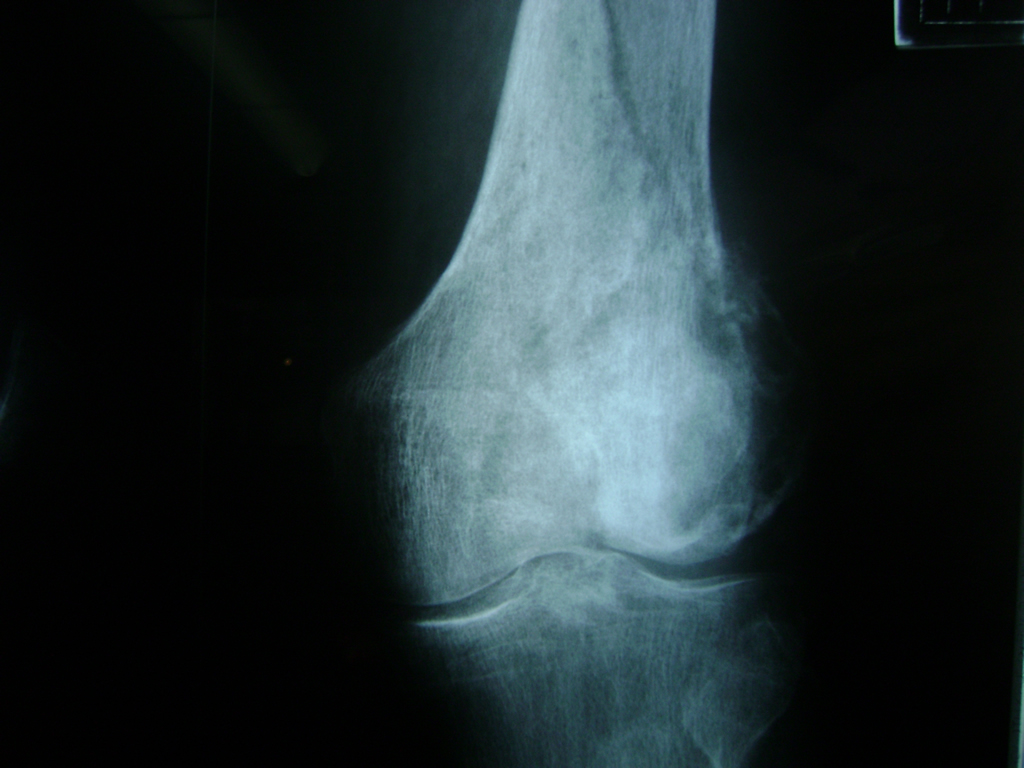

La artroscopia de rodilla es un cirugía en el cual la estructura interna de la articulación es examinada ya sea para realizar un diagnostico o para realizar un tratamiento, este procedimiento se realiza utilizando un instrumento parecido a un pequeño tubo llamado artroscopio.